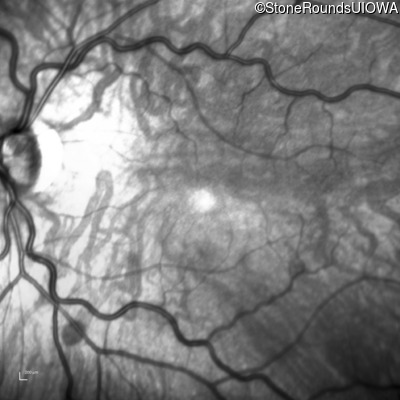

Age at visit: 26 years

This 26 year old man had significant myopia since childhood and uncorrectable reduction of acuity since his mid teens. Optic nerve abnormalities were noticed on a routine exam at age 5 and a diagnosis of Retinitis Pigmentosa was suggested. His medical history is also positive for profound hearing loss at birth and type 1 diabetes mellitus.